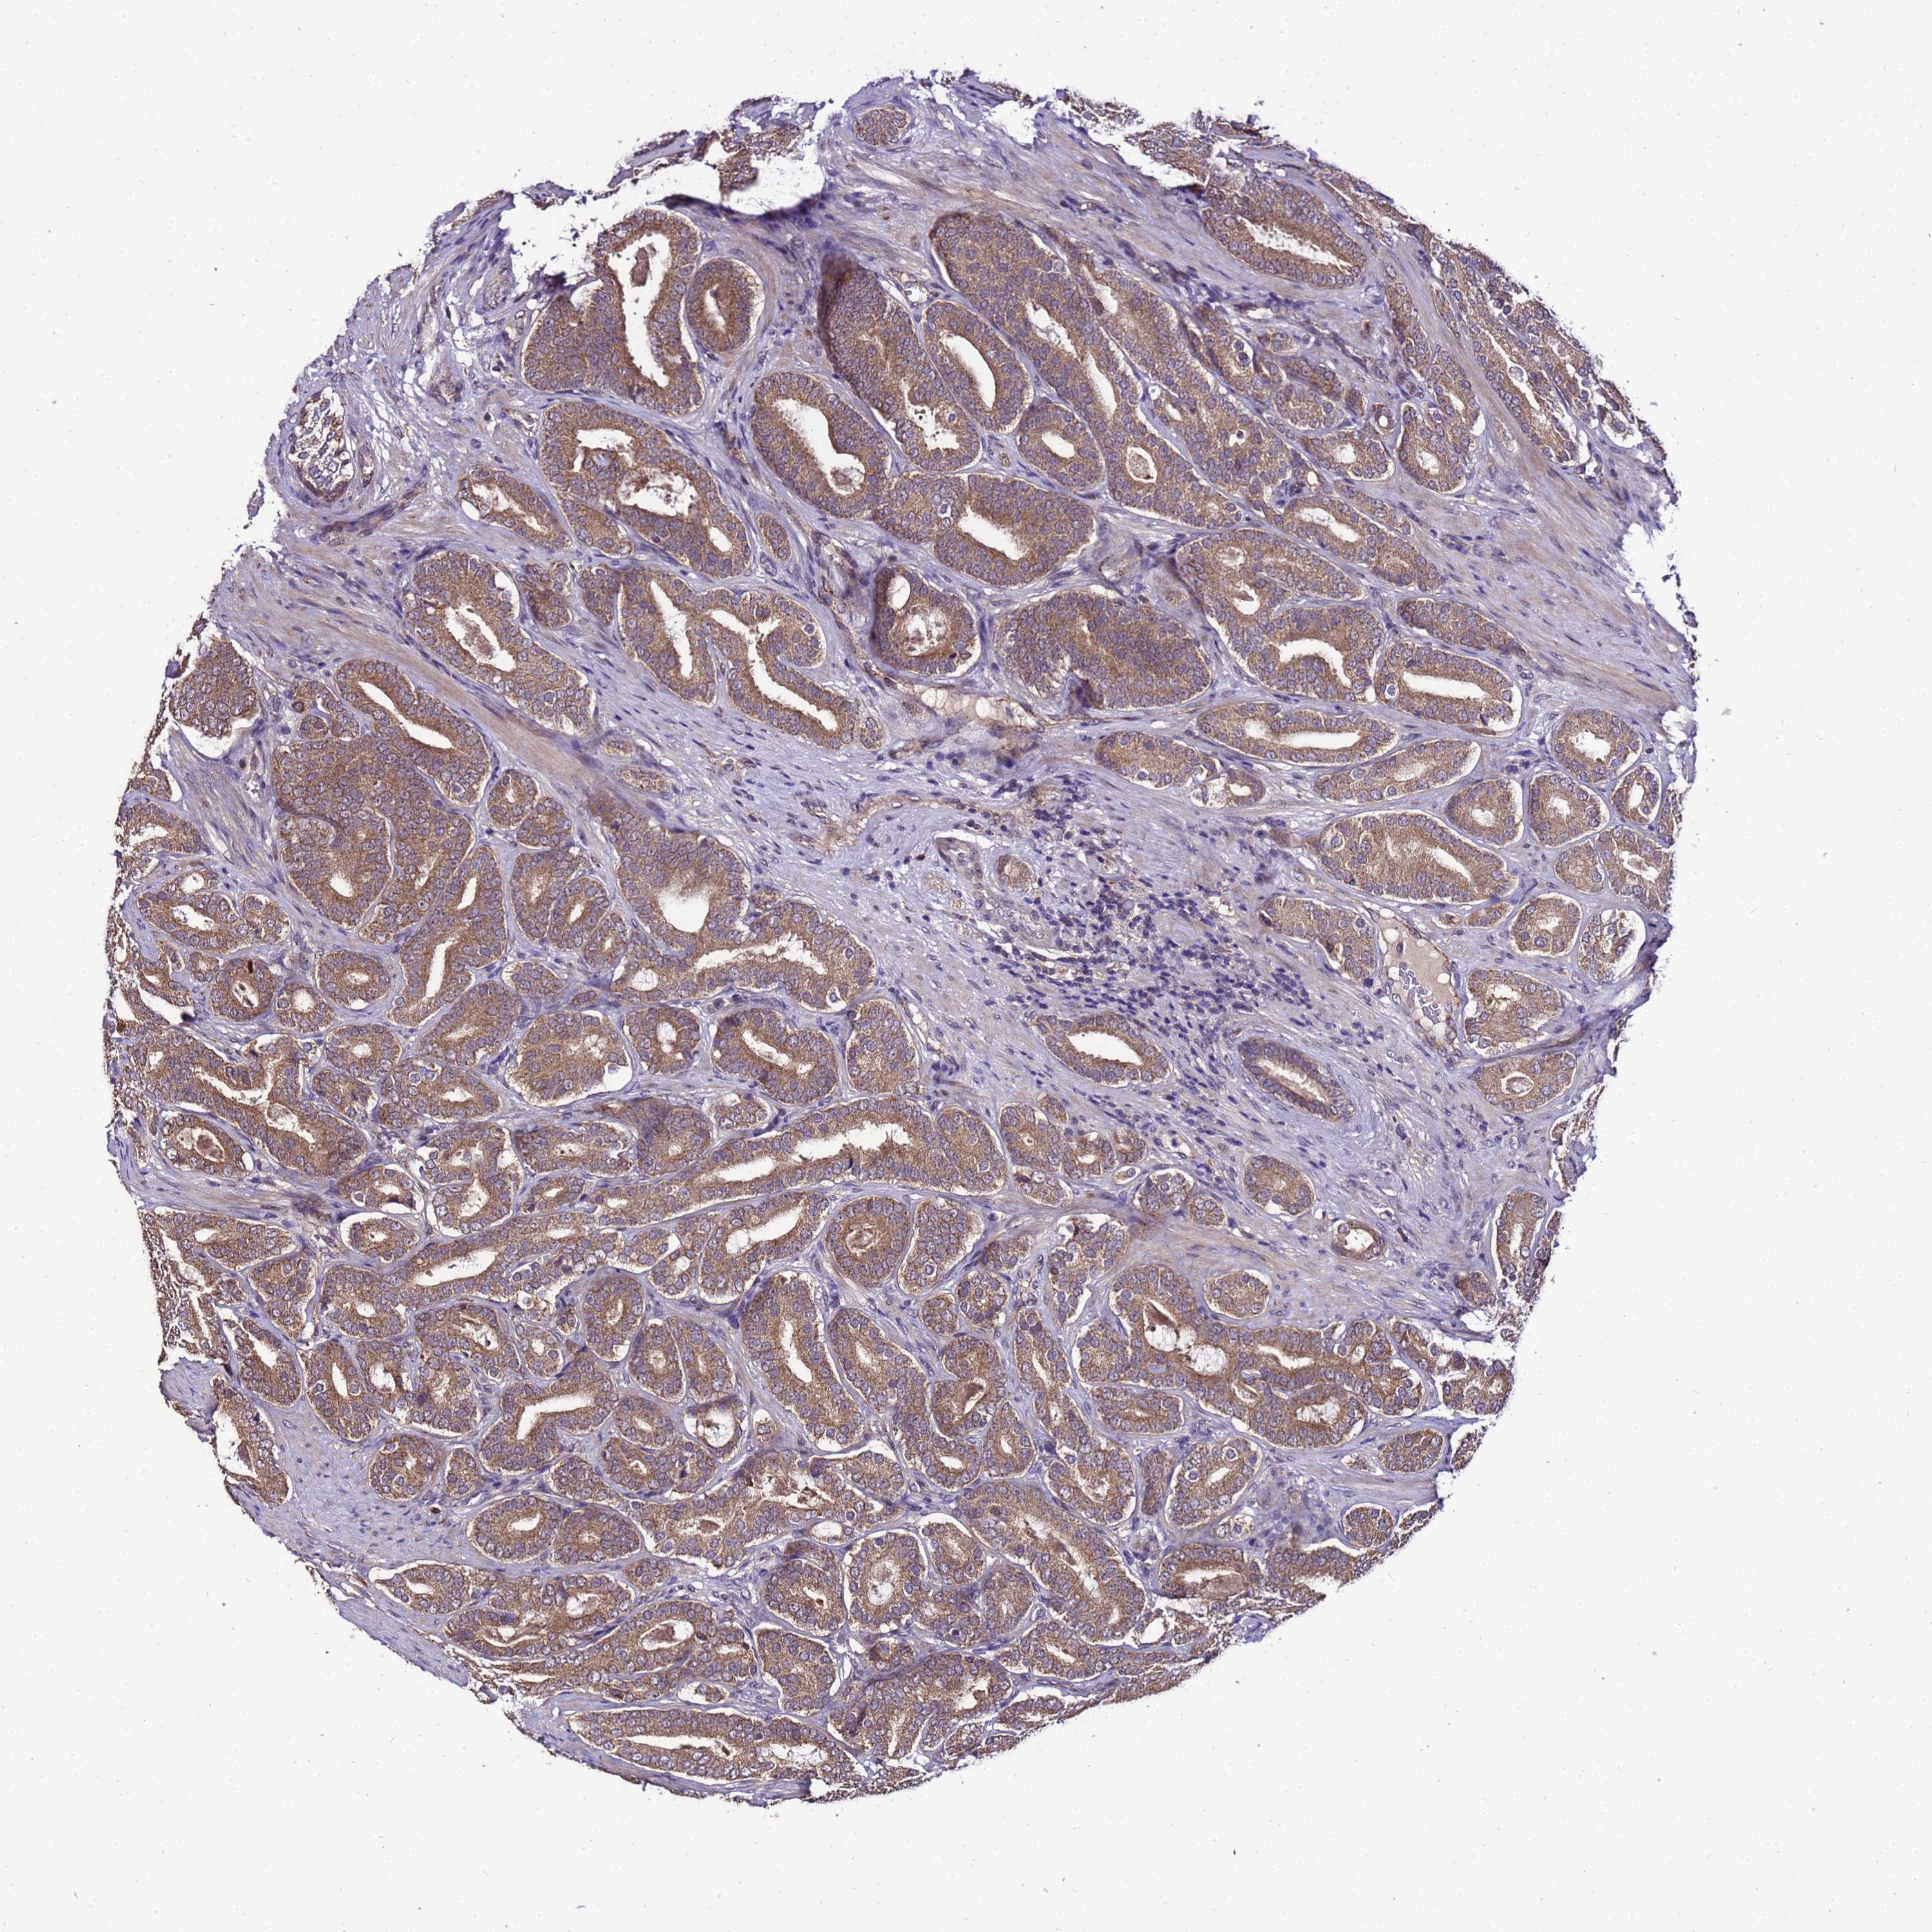

PROSTATE CANCER - Protein expressioni

A mouse-over function shows sample information and annotation data. Click on an image to view it in a full screen mode. Samples can be filtered based on level of antibody staining by selecting one or several of the following categories: high, medium, low and not detected. The assay and annotation is described here.

Note that samples used for immunohistochemistry by the Human Protein Atlas do not correspond to samples in the TCGA dataset.

Antibody stainingi

Antibody staining in the annotated cell types in the current human tissue is reported as not detected, low, medium, or high, based on conventional immunohistochemistry profiling in selected tissues. This score is based on the combination of the staining intensity and fraction of stained cells.

Each image is clickable and will lead to virtual microscopy that enables deeper exploration of all samples and also displays staining intensity scores, fraction scores and subcellular localization as well as patient and tissue information for each sample.

Antibody HPA044373

Staining

High

Medium

Low

Not detected

Intensity

Strong

Moderate

Weak

Negative

Quantity

>75%

75%-25%

<25%

None

Location

Nuclear

Cytoplasmic/membranous

Cytoplasmic/membranous,nuclear

Adenocarcinoma, NOS

Adenocarcinoma, High grade

Adenocarcinoma, Low grade